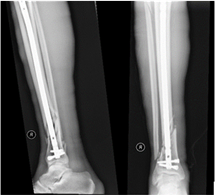

We reviewed the radiological results of patients treated in our institution for closed fractures of the distal tibia during the period January 2013 to December 2017. Ethical clearance was obtained from the university’s research and ethics committee (Ref 422/2022), we included fractures classified as AO 43A10 and fractures that are 4-11cm above the tibial plafond (Figure 1 & 2). We excluded segmental fractures, intraarticular fractures, fractures in patients less than 18yrs of age, pathological fractures, patients with previous fractures of the tibia and fractures treated by any method other than the two under investigation.

Figure 1 AO Classification.

Figure 2 Distal tibia fracture.